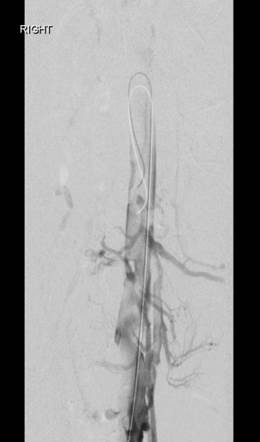

Acceso poplíteo; vista de posición decúbito prono de un trombo oclusivo agudo en la vena poplítea izquierda y en la vena femoral.

Acceso poplíteo; vista de posición decúbito prono de un trombo oclusivo agudo en la vena femoral izquierda y en las venas ilíacas.

Vena femoral izquierda duplicada, vena femoral común izquierda y VCI de la vena ilíaca externa tras trombectomía mediante el catéter Solent de AngioJet; 25 mg tPa en 250 cc de solución salina (Rapid Lysis) y stent de 14 mm.